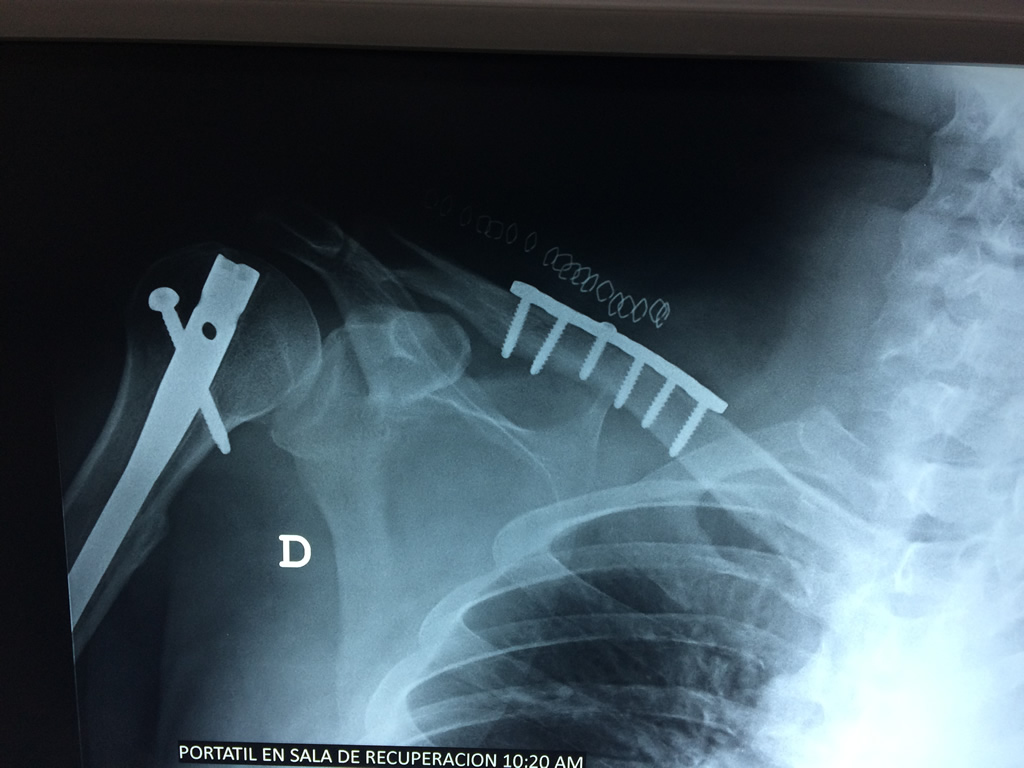

Cirugías de Hombros - Clavícula

La clavícula es un hueso largo, con forma de "S" itálica, situado en la parte anterosuperior del tórax. Junto con la escápula forman la cintura escapular. Se puede palpar por toda su longitud y se extiende del esternón al acromion de la escápula, siguiendo una dirección oblicua lateral y posterior.